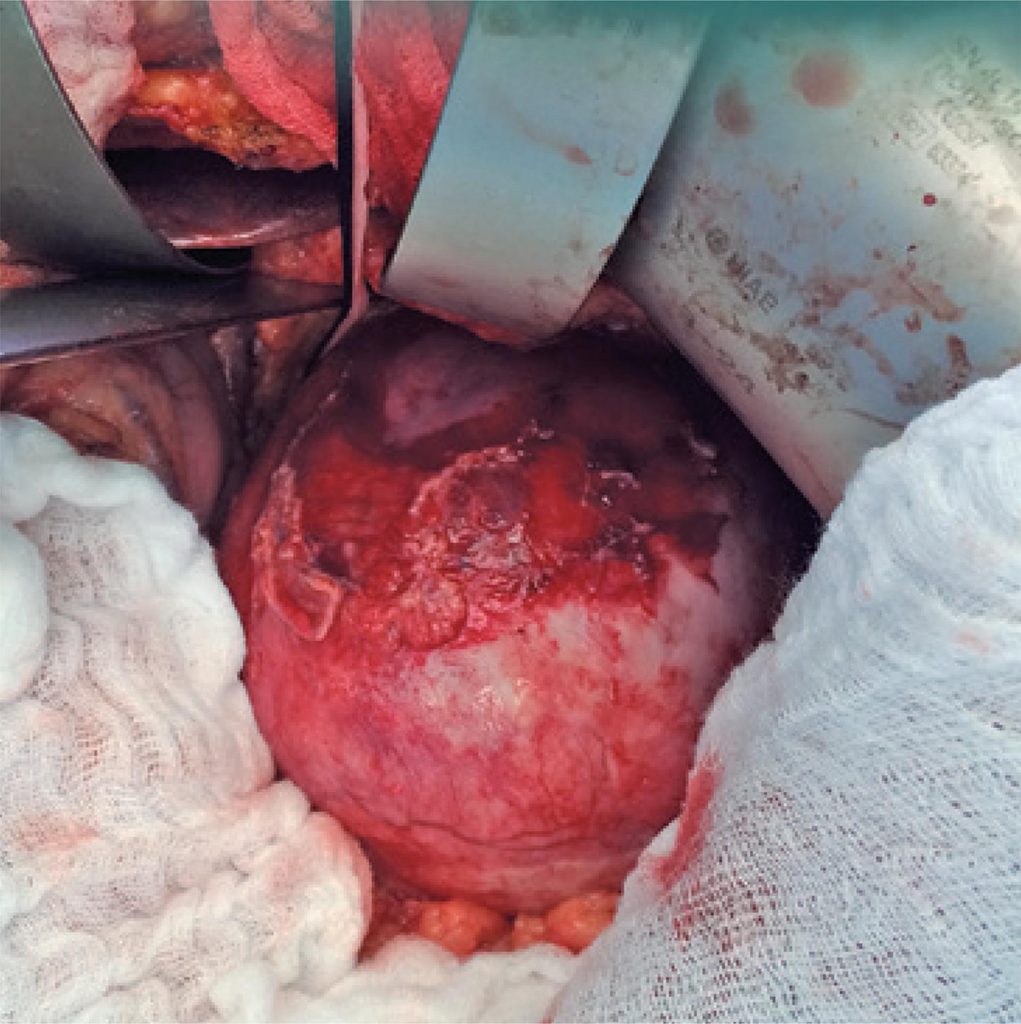

O aneurisma gigante da artéria esplênica constitui condição rara, que representa risco de vida iminente para o paciente, necessitando, consequentemente, de correção cirúrgica urgente. Mulher de 61 anos, ex-fumante, hipertensa, com hipercolesterolêmica e multípara nos procurou por apresentar grande tumor no mesogástrio, achado de ultrassonografia abdominal. Apesar das dimensões do tumor, era assintomática. Angiotomografia e ressonância magnética de abdômen sugeriam tratar-se de aneurisma gigante de artéria esplênica com mais de 10cm de diâmetro, confirmado por angiografia. Foi submetida a tratamento cirúrgico aberto, tendo sido realizadas esplenectomia e aneurismectomia parcial. A abordagem do tronco celíaco, que foi ligado, só foi possível com rotação visceral medial, pois não havia possibilidade de visualizá-lo pela via anterior. O exame anatomopatológico da parede do saco aneurismático revelou placas de ateroma na íntima. A paciente evoluiu sem intercorrências e teve alta hospitalar curada. Aneurismas da artéria esplênica de dimensões avantajadas, em geral, são sintomáticos, porém, como no caso em questão, podem ser assintomáticos e descobertos em exame de imagem do abdômen. Apesar de existirem métodos intervencionistas menos invasivos, como laparoscopia e técnicas endovasculares, eles não foram considerados adequados neste caso. Diante de um aneurisma gigante de artéria esplênica, a conduta terapêutica de eleição é a cirurgia convencional aberta.